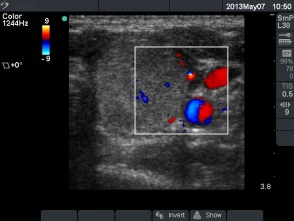

First session of sclerotherapy (1st row of images)

Clinical presentation: a 27-year-old woman was referred for evaluation of a multinodular goiter. The lesion in the left lobe has increased in the past two years and caused neck discomfort.

Palpation: a not firm nodule in the left lobe.

Functional state: euthyroidism with TSH 0.93 mIU/L, FT4 14,3 pM/L.

Ultrasonography: the thyroids were echonormal. There was a small lesion with a maximal diameter of 7 mm in the right lobe and a larger nodule in the left lobe. Both were echonormal.

Aspiration cytology resulted in benign colloid goiter.

We suggested surgery because of the compression signs. The patient told us that she is a cook in a seafarer and she has the opportunity to miss from the work only for a couple of weeks in the subsequent years. We advised ethanol sclerotherapy. Six sessions of ethanol was given. A total amount of 13.7 mL ethanol was administered in six session in 5 weeks.